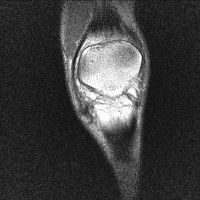

무릎 mri 간단히 봐주실 수 있으시나요 ㅠㅠ

안녕하세요 8년전 십자인대 수술하고 최근 무리한 운동에 무릎 불편감이 생겨서

mri 찍었습니다.

진단결과는 첫 찍은 병원에서 활액막염 이라는 진단을 받았습니다. 혹시 봐주실 수 있으실까요?

올라온 MRI가 단편적이라서 정확한 진단에 어려움이 있지만 십자인대에는 큰 이상이 있지는 않은것 같으며, 무릎관절내 물이 있는 것으로 보아 활액막염의 진단이 맞을 것 같습니다.

하지만 단편적인 영상이기 때문에 촬영병원에서 정확한 판독지 등을 받으시는 것이 좋겠습니다.